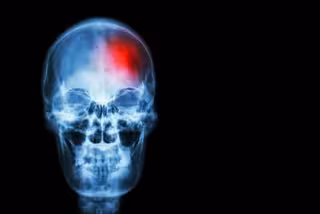

¿Por qué la Covid-19 aumenta el riesgo de infartos e ictus?

Archivo - Ictus

Los expertos llevan tiempo observando que el coronavirus COVID-19 aumenta la probabilidad de sufrir un infarto de miocardio o un ictus hasta un año después de la infección, sobre todo en quienes ya padecen afecciones cardiacas subyacentes. Sin embargo, hasta ahora no estaban claros los mecanismos específicos que explican estos riesgos.